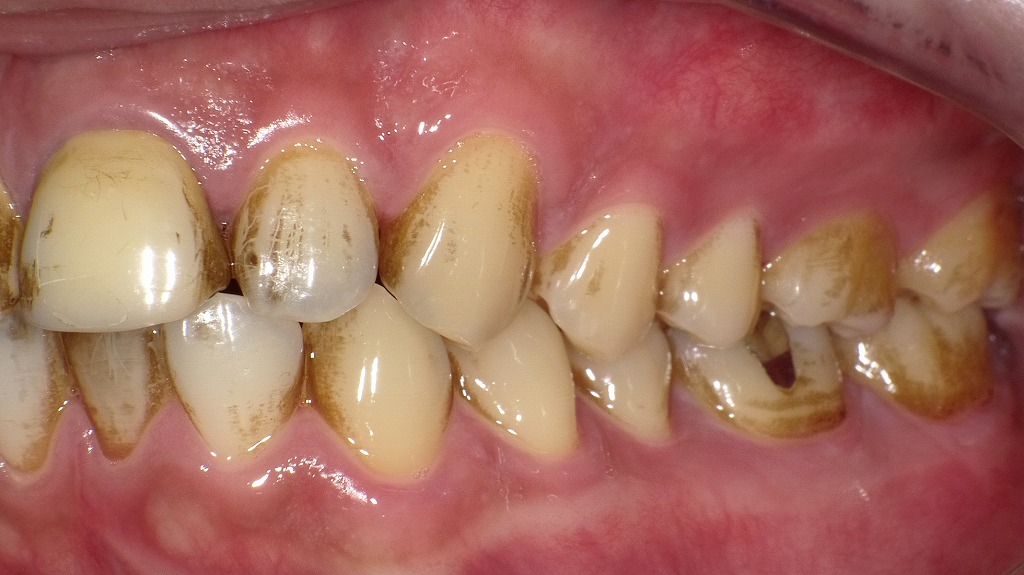

■ホワイトニングの症例

1枚目:ホワイトニング前

歯全体に強い黄ばみが見られ、特に上の前歯部には濃い変色があります。左上1番は欠損しており、前歯のバランスも崩れています。また、上下の前歯には咬耗があり、全体的にくすんだ印象です。